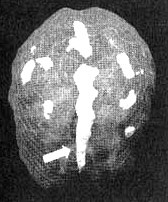

Поясная извилина

Иллюстрация к книге — Измените свой мозг - изменится и жизнь! [i_056.jpg]

Трехмерное изображение — активный мозг